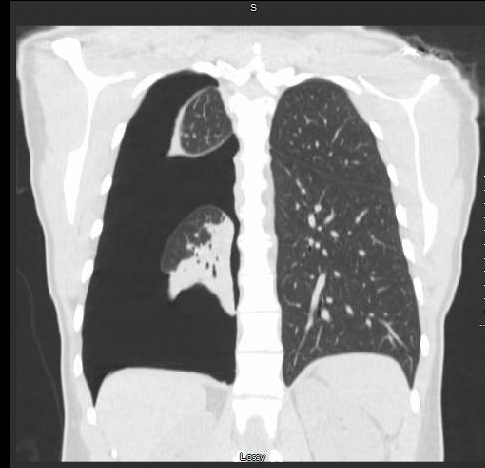

Case Presentation: 41 Years old Caucasian female with a past medical history of pleurisy since a year and iron deficiency anemia was present to the ED with three days history of right-sided chest pain and difficulty in breathing. – Vitals stable and chest x-ray, and CT of the chest showed sizeable right-sided pneumothorax got chest tube placement and repeat chest x-ray was showing re-inflation of lungs.

– But patient continued to have chest pain. Repeat CT chest which showed no improvement in the pneumothorax and trapped lung.